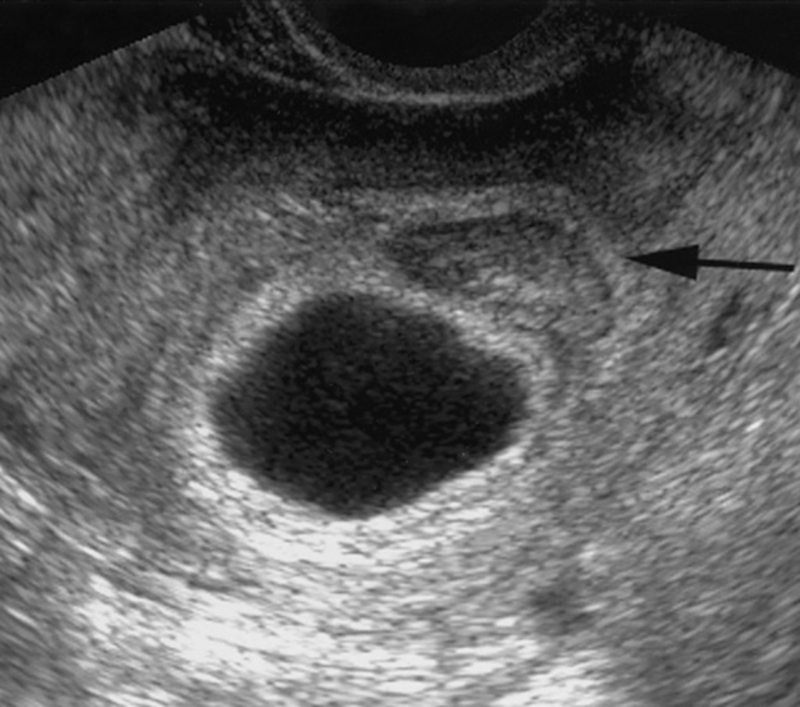

Túi yolksac hay còn được gọi là túi noãn hoàng thường được tìm thấy trong quá trình siêu âm tuần thứ 5 của thai kỳ. Túi yolksac có kích thước tương đối nhỏ, khoảng bằng hạt vừng nhưng có vai trò rất quan trọng. Sự xuất hiện của yolksac là đánh dấu sự chuẩn bị cho sự hình thành nhau thai sau này.

Thai khi siêu âm không có yolksac là khoảng từ tuần thứ 5 trở đi, khi siêu âm không quan sát được hình ảnh của túi này. Túi noãn hoàng không phát triển ảnh hưởng rất nghiêm trọng đến thai nhi vì chức năng chính của nó là chuyển hóa, truyền dinh dưỡng cung cấp cho sự phát triển của phôi thai.

Dù đóng vai trò quan trọng nhưng túi yolksac chỉ tồn tại ở giai đoạn đầu của thai kỳ. Đến khi tuần hoàn nhanh thai đi vào ổn định, túi yolksac sẽ biến mất dần dần nhường lại chức năng nuôi dưỡng cho nhau thai. Nếu siêu âm ở tuần thứ 6 vẫn không tìm thấy hình ảnh của túi yolksac thì mẹ bầu nên đi khám chuyên khoa để được tư vấn về tình trạng thai kỳ.

Túi yolksac là gì? Siêu âm không có yolksac ảnh hưởng nghiêm trọng đến sự hình thành và phát triển của thai nhi